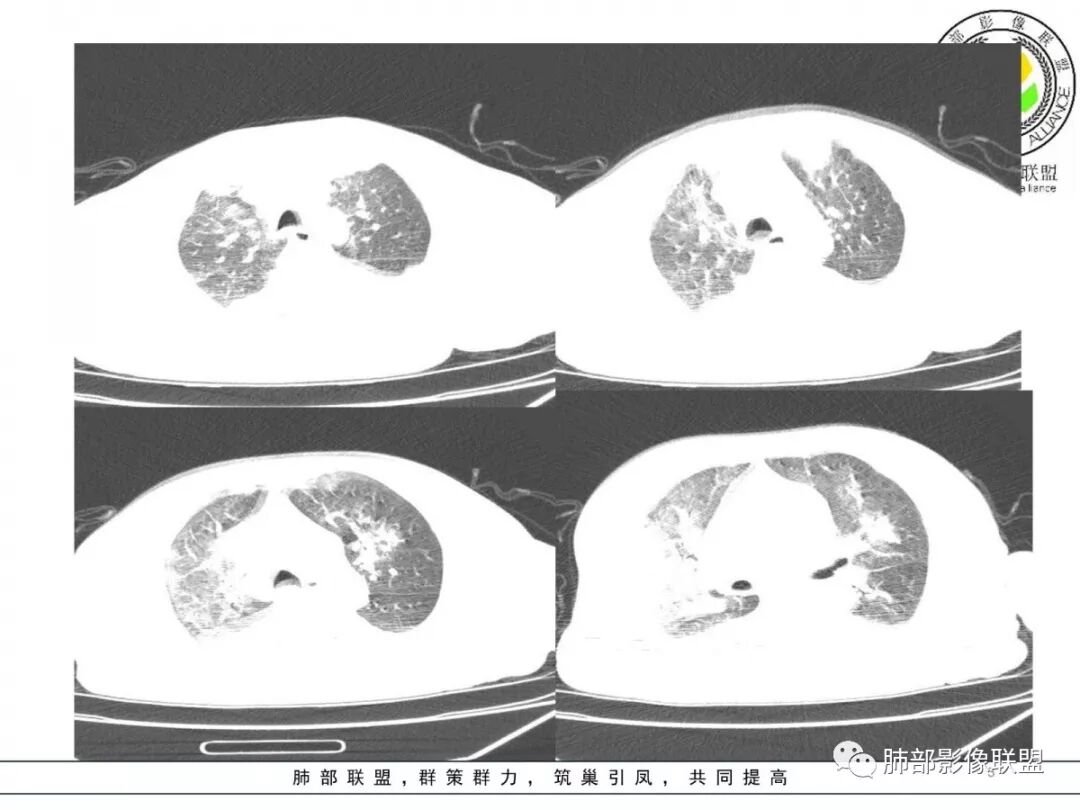

双肺以肺门为中心分布为主多发片状影,边缘模糊,部分小叶间隔有增厚,双侧胸腔积液,心影增大,考虑心衰、肺水肿。

老年男性,突发胸闷憋喘。蝶翼征、套袖征、肺静脉增粗、小叶间隔增厚,胸腔积液,心脏增大,符合心衰肺水肿,常规治疗后复查除外合并其它。

双肺小叶间隔增厚,多发片影,从肺门向外分布,双胸水,上感史,双肺水泡,诱发心功能不全丶肺水肿。鉴别病毒肺并心衰,单独病毒出水少见,有意识不清,心衰少见,鉴别脑血管病引起的吸入丶神经源性肺水肿。是否合并PE待查

双肺弥漫对称边缘模糊斑片影,右肺为著,肺门影增大,双侧胸腔积液,左心增大 ,肺水肿。鉴别真菌,真菌很少有胸腔积液,肺泡出血,临床没有咳血。

双肺大片渗出影,以肺门为主,支气管血管束明显增粗,心影增大,左心室明显增大,双侧胸腔积液。诊断心衰,鉴别病毒肺这个病人应该同时还有贫血。。

两肺渗出,胸膜腔积液,左室显著增大,首先考虑肺水肿,建议治疗后复查。左肺上叶舌段病灶似有支气管截断征。

双肺近肺门斑片样阴影,以双下肺分布较明显,小叶间隔增厚,心影大,双侧胸腔少_中等量积液,所见层面支气管未见明确狭窄,根据病史,吸入性肺炎不能除外,急性肺水肿。

心脏增大,以左心室增大为主,胸腔积液,以右侧为甚,小叶间隔增厚——左心衰竭?肺主动脉增宽——肺动脉高压?左肺上叶前段以及肺门处见多个斑片状高密度影——感染(类型:细菌?病毒?),不像肺水肿分布改变

两肺大片状实变影,中内带为主,边缘稍模糊

周围大片GGO

小叶间隔增厚